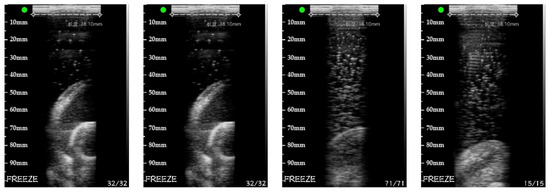

The real target experimental data are shown in Figure 24. When acquiring images, because it is a freehand probe, the distance between the probe and the target is uncertain. The medium of the container is also non-uniform. Figure 24 is a set of the cross-sectional images collected by the probe at various points in space. Figure 25 is the reconstructed image of the real target with the PSM.

Figure 24.

Cross-sectional images collected by the probe.